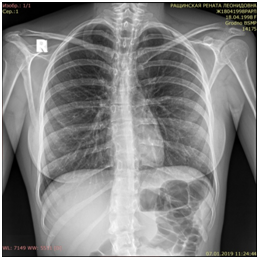

The first period of labor proceeded without complications, antispasmodic and metabolic therapy was carried out. The duration of the first period of labor was 7 hours 25 minutes, the second period - 1 hour, the third period - 15 minutes. A live male child was born weighing 3350 g, height 53 cm, 8/9 points according to Apgar. Blood loss was 450 ml. One hour after the birth, a feeling of fullness of the neck, face, pain behind the sternum appeared, the voice changed, the tongue increased, speech was disturbed, breathing became difficult, hyperemia of the face, eyelids overhanging the eyeballs appeared. Initially, this condition was regarded as Quincke's edema. Later, upon palpation of the anterior surface of the chest to the eighth rib, arms, neck, face (more to the left), crepitus of the subcutaneous tissue appeared. Shortness of breath began to increase up to 28 respiratory movements per minute, tachycardia up to 104 per minute, hypotension (blood pressure 80–90 / 50 mm Hg). Above all fields of the lungs, weakened breathing was heard. The surgeon on duty was called. Performed X-ray examination (Figure 1).

Figure 1 Chest x-ray of patient R. showing pneumomediastinum.

Diagnosed with spontaneous mediastinal emphysema. On the x-ray of the chest organs (see Figure 1) in the supine position, the transparency of the pulmonary fields is reduced due to the large accumulation of air in the soft tissues of the chest. The mediastinal shadow is located in the middle, the sheets of the mediastinal pleura are “stratified” by an accumulation of air. The heart is bordered by a strip of air. On the radiograph in a lateral projection, the presence of air in the anterior sections of the mediastinum is clearly defined. Conclusion: X-ray picture of mediastinal emphysema, subcutaneous emphysema. Ultrasound imaging of the chest organs is impossible due to the high pneumatization of the subcutaneous tissue, no signs of free fluid in the chest were detected. On the electrocardiogram there is a slight deviation of the electrical axis of the heart to the left, moderate changes in the myocardium of the left ventricle, mainly of metabolic and metabolic nature.